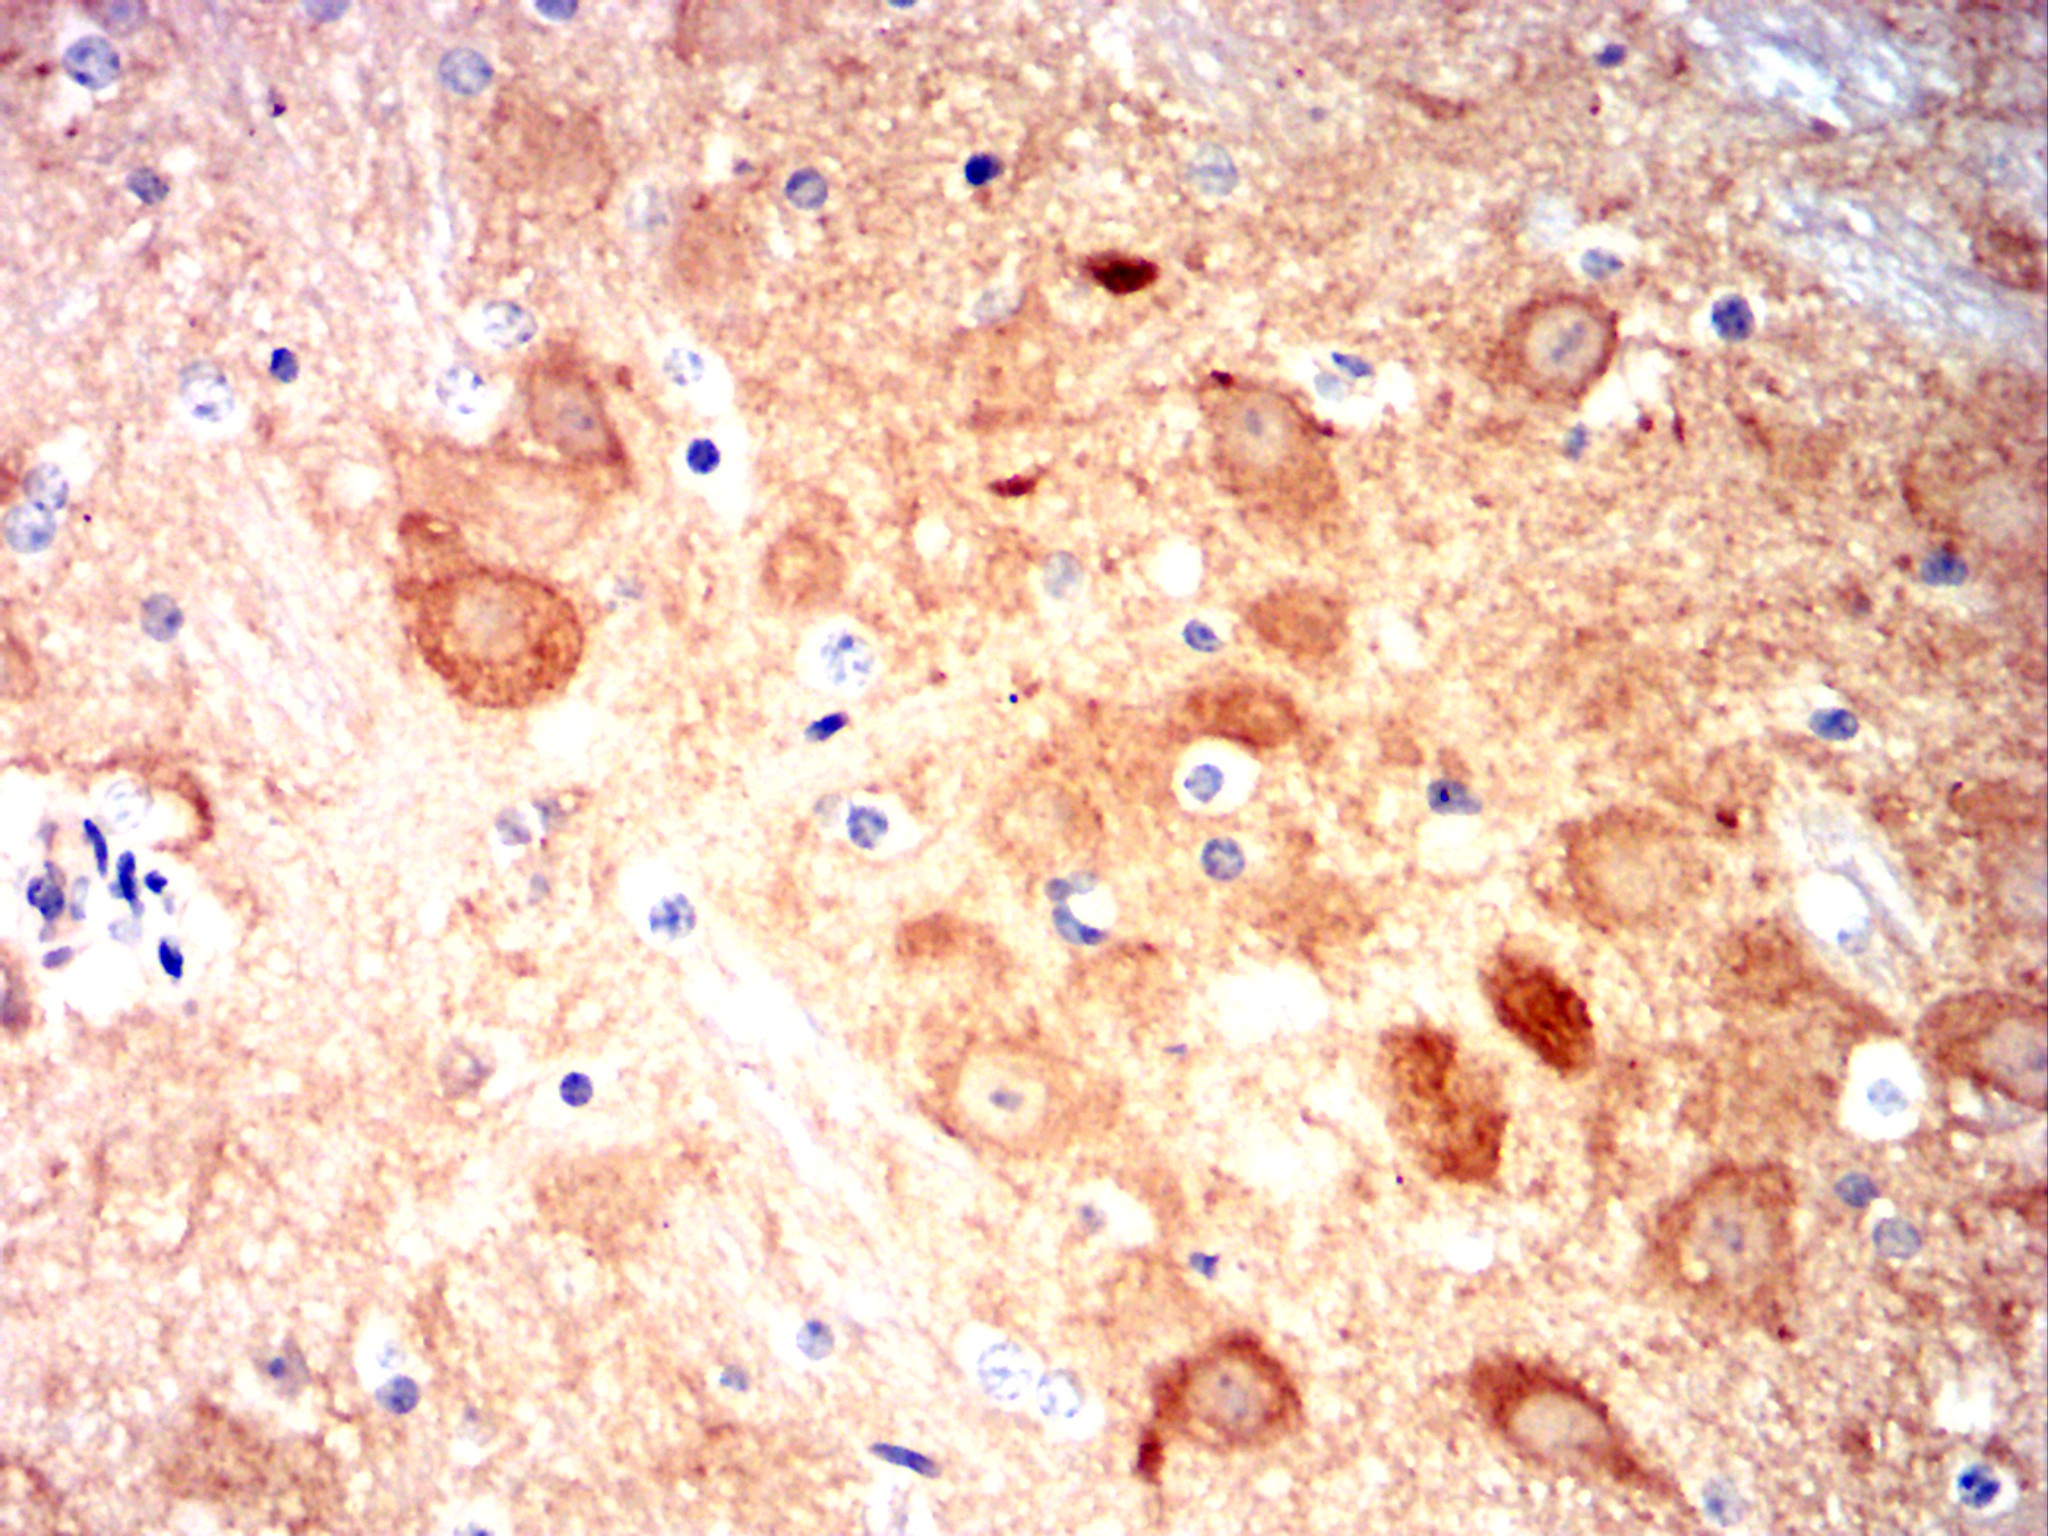

Immunohistochemical analysis of paraffin-embedded Mouse cerebellum using CAMK2G mouse mAb with DAB staining.